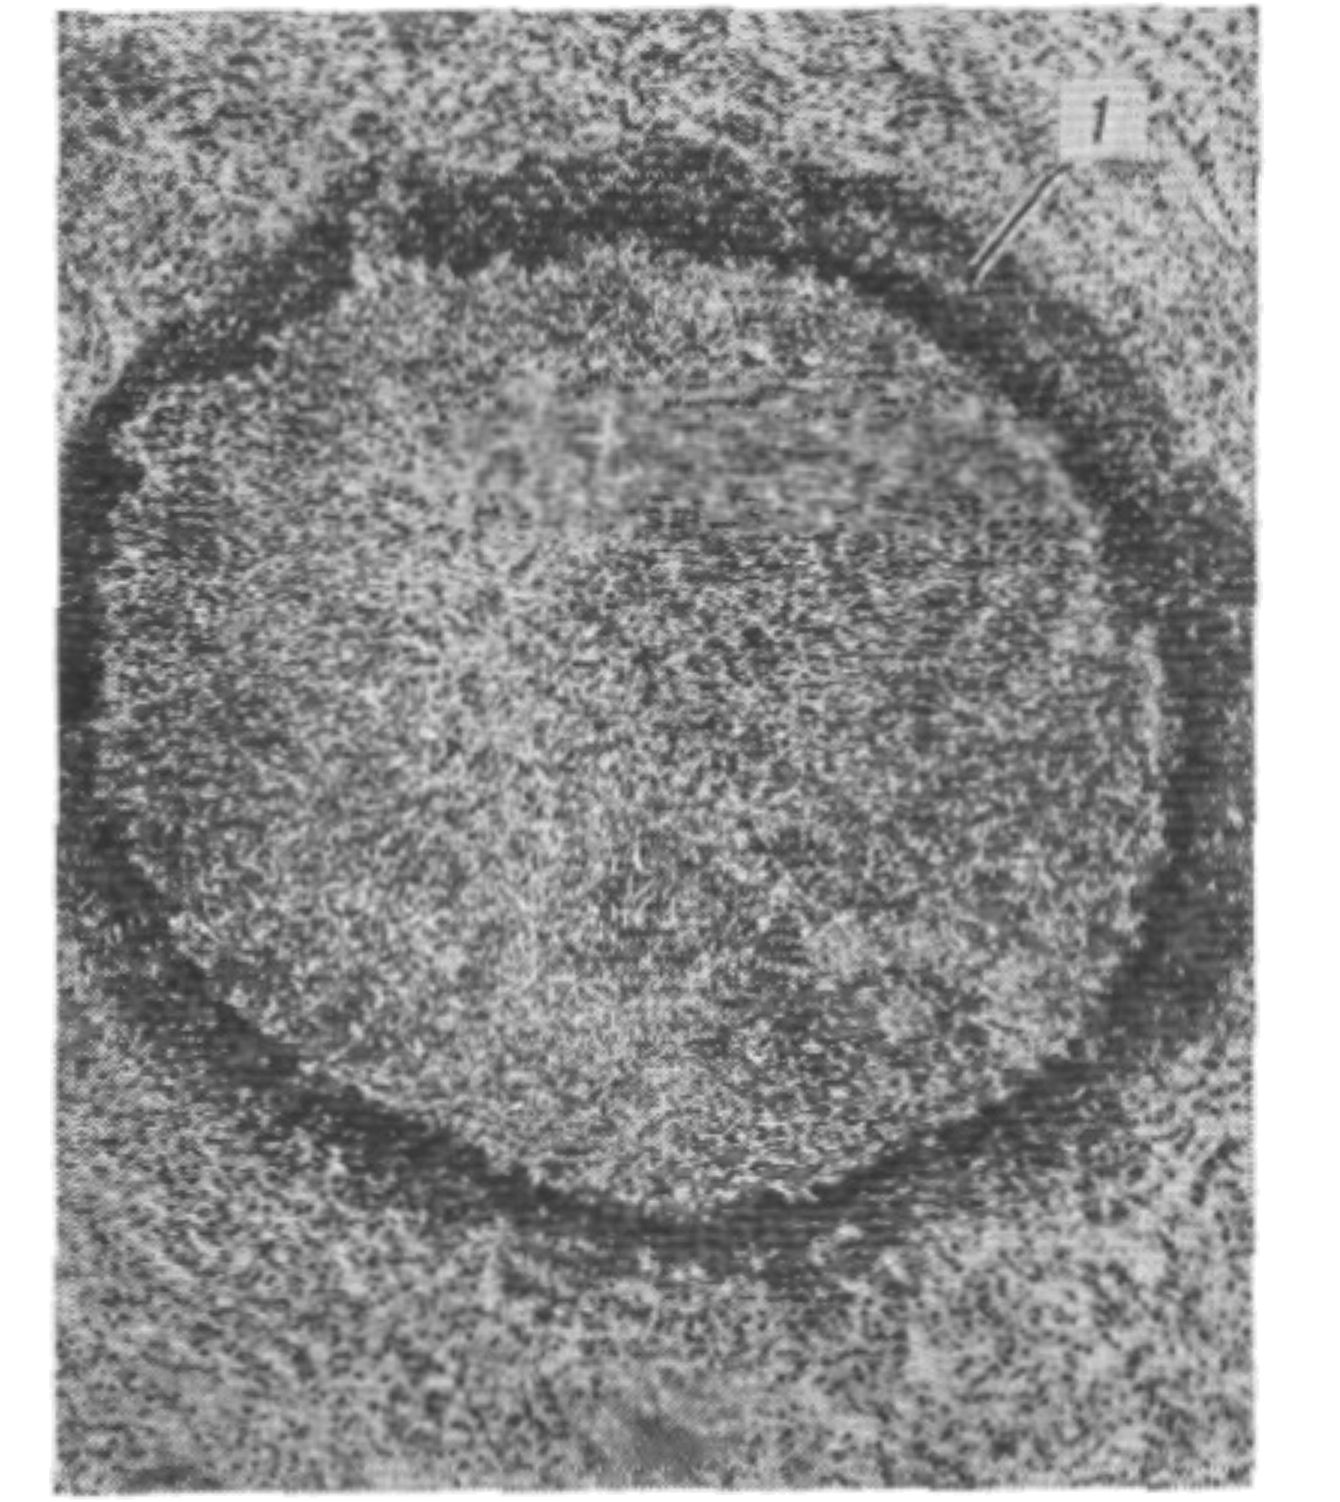

Рис. 1. Острый абсцесс. Участок ткани, инфильтрированный гнойным экссудатом. Скопление лейкоцитов по периферии абсцесса (1).

В начальном периоде формирования Абсцесс инфильтрируется воспалительным экссудатом и лейкоцитами ограниченный участок ткани. Постепенно под влиянием ферментов лейкоцитов ткань подвергается расплавлению, и образуется полость, заполненная гнойным экссудатом. Форма полости может быть как простой округлой, так и сложной, с многочисленными карманами.

Стенки Абсцесса в ранней стадии его формирования покрыты гнойно-фибринозными наложениями и обрывками некротизированных тканей. В дальнейшем по периферии Абсцесса развивается зона демаркационного воспаления, составляющий ее инфильтрат служит основой для формирования пиогенной мембраны, образующей стенку полости (рис. 1). Пиогенная мембрана представляет собой богатый сосудами слой грануляционной ткани. Постепенно в той ее части, которая обращена в сторону окружающих Абсцесс тканей, происходит созревание грануляций. Таким образом, если Абсцесс приобретает хроническое течение, в пиогенной мембране образуются два слоя: внутренний, обращенный в полость и состоящий из грануляций, и наружный, образованный зрелой соединительной тканью (рис. 2).